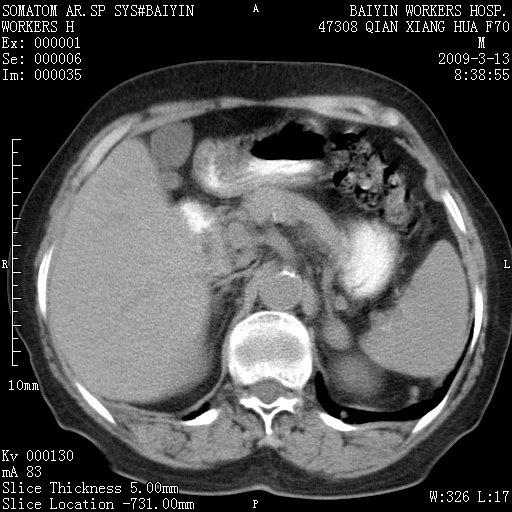

标题: CT18651:左肾上腺占位,请会诊! [打印本页]

标题: CT18651:左肾上腺占位,请会诊!

女,70岁,体检发现。

左侧肾上腺结节状软组织密度影;考虑肿瘤(肾上腺腺瘤?转移瘤?)。

左侧肾上腺占位,腺瘤?不除外转移。

左侧肾上腺占位,腺瘤可能。

左侧肾上腺占位,考虑腺瘤可能。